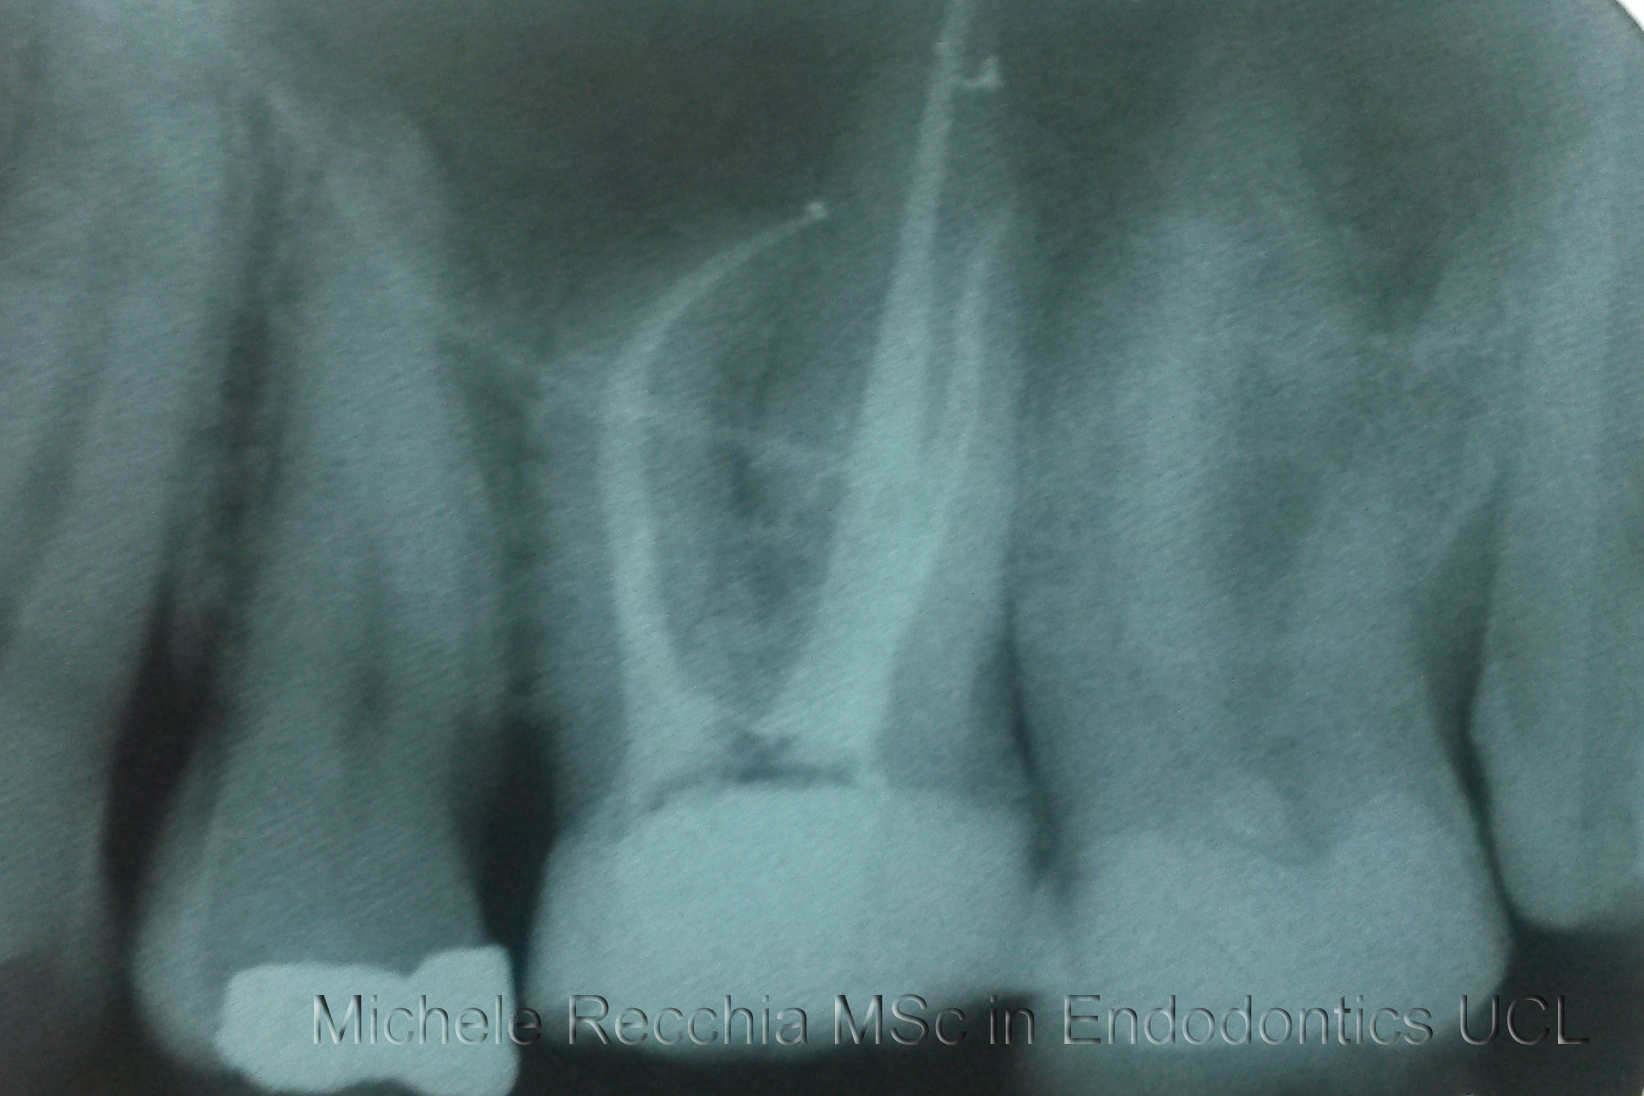

Root canal treatment is the process of going inside the pulp space and removing the infected dead tissue. The space is then disinfected and sealed with special materials.